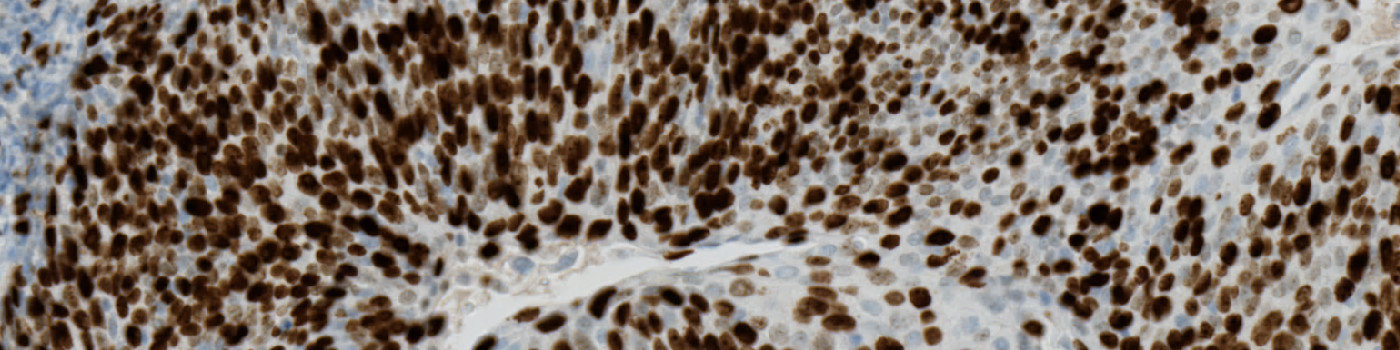

The Ki-67 protein is associated with cellular proliferation, and the protein is present in the nucleus of all cells that are in the active phase of the cell cycle, but absent in resting cells, see [1]. The cell proliferation rate can be assessed by Ki-67-immunohistochemical (IHC) staining, and this can be correlated to the tumor grade and the clinical course, see [2].

This protocol can be used to assess tumors by determining the Ki-67 positivity.

Ki-67 negative and positive nuclei are detected and delineated from their surroundings to accurately quantify nuclei in highly concentrated areas.